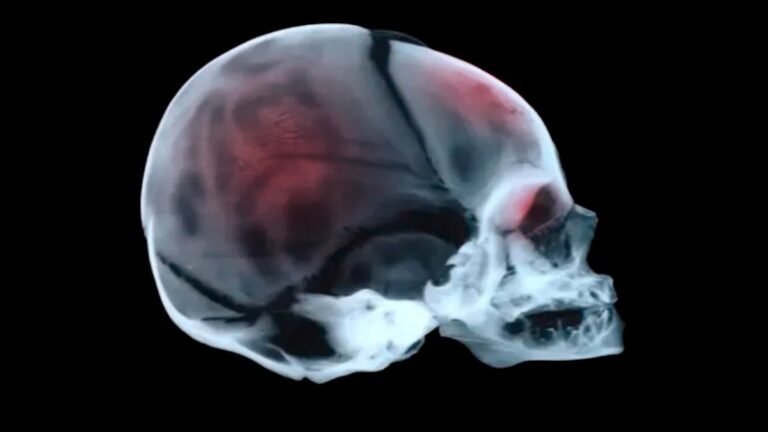

The latest episode of the podcast Diagnosing Murder, released over the weekend, delves into...